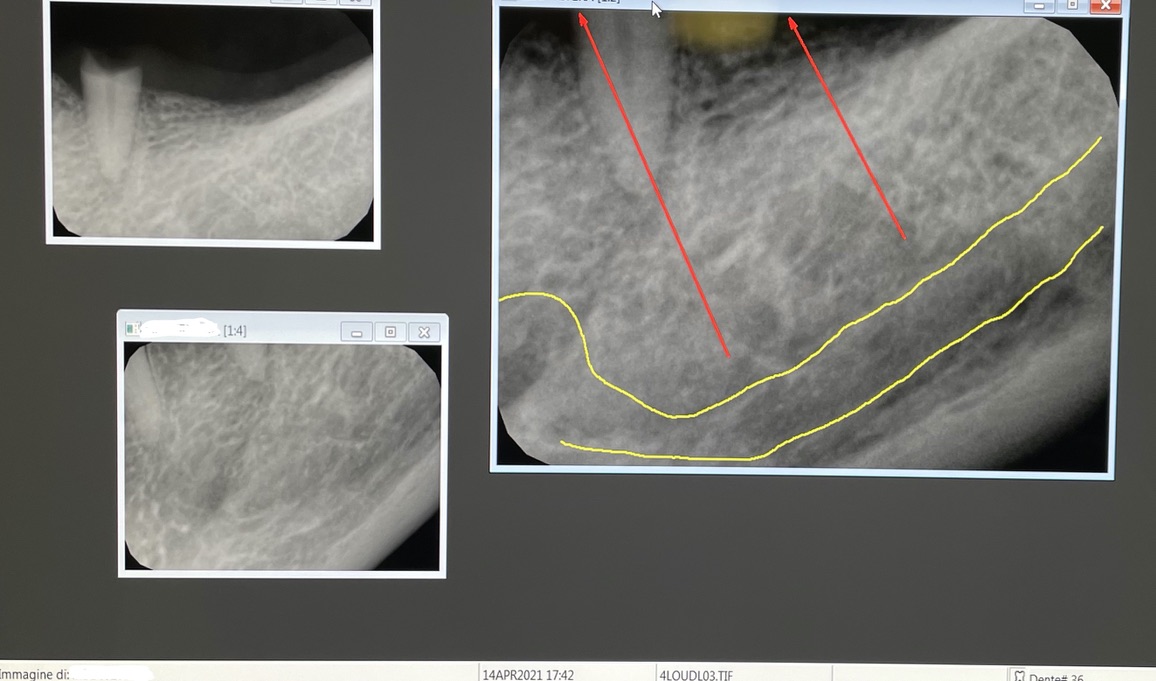

1 - UN CASO INCISIVO

Frattura di elemento incisivo inferiore 31 e riabilitazione implantare